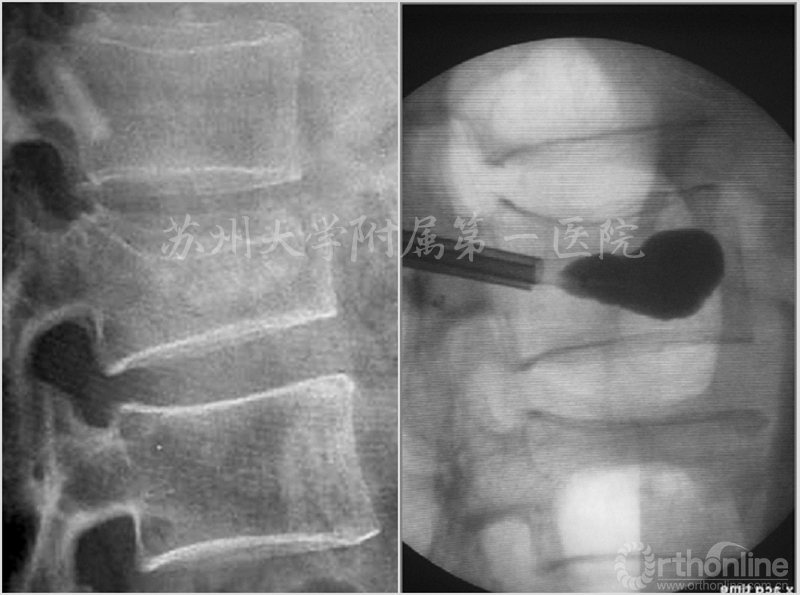

KP手术操作流程简介:a.经皮穿刺骨折椎体置入球囊;b.扩张球囊骨折复位;c.灌注骨水泥固定骨折椎体

患者刘×,男性,70岁,腰2骨质疏松性椎体骨折,经皮置入球囊扩张后骨折复位